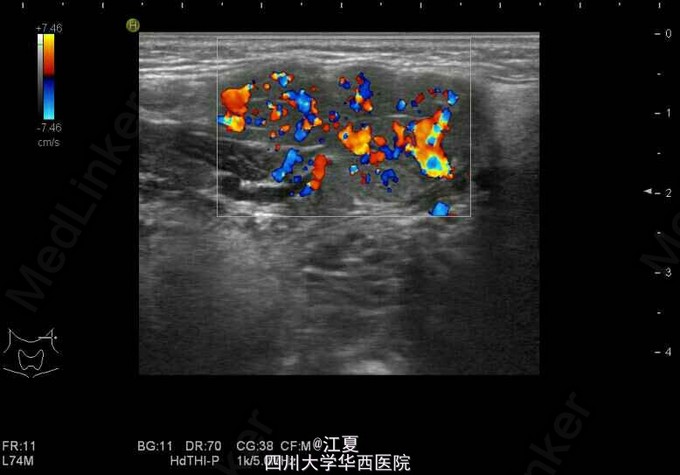

患者,女,19岁。发现颈部包块3月余。

包块无红肿,有轻微触痛。 超声示:左侧颌下腺长大,前后径约18mm,颌下腺导管增粗,最粗约5mm,内查见大小约4mm的强回声团伴声影。

诊断:左侧颌下腺导管结石伴扩张,左侧颌下腺长大。 治疗:摘除涎石(碎石机粉碎或手术)。症状较轻者可口服排石汤或其他辅助药物。预防应多饮水或进食酸性食品,促使唾液分泌,可使小涎石自行排出。